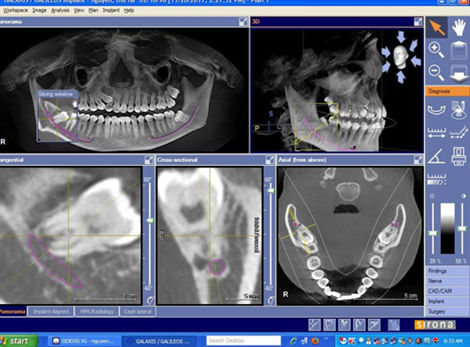

| - Ứng dụng trong chỉnh nha: Với phim chụp CBCT, bác sĩ chỉnh nha có thể coi tình trạng răng ngầm, hướng mọc của các răng, tương quan và sự phát triển xương hàm, vị trí xương để đặt minivis, phân tích các thông số chỉnh nha về thẩm mỹ khuôn mặt, đánh giá kết quả trước và sau khi chỉnh nha của bệnh nhân. | | |

| - CBCT trong việc lập kế hoạch điều trị Implant sử dụng hình ảnh 3D và đa lớp cắt để xác định chính xác chiều cao, độ rộng và giải phẫu của phần xương hàm và xương ổ răng cũng như mối tương quan vùng mất răng với cấu trúc giải phẫu liền kề như ống thần kinh răng dưới. Đặt Implant với máng hướng dẫn phẫu thuật có thể được thực hiện với các dữ liệu CBCT. Với khả năng 3 chiều của CBCT, các nhà lâm sàng có thể quyết định liệu có cần đến việc ghép xương, nâng xoang trước khi đặt Implant hay không cũng như chọn kích thước implant phù hợp nhất cho từng vùng xương. | | |

| - CBCT trong chẩn đoán răng khôn mọc lệch/ mọc ngầm: Nhờ có sự giúp đỡ của CBCT, bác sĩ có thể lường trước được mối liên quan của dây thần kinh với chân răng khôn cũng như quyết định thực hiện kỹ thuật nhổ răng khôn trong một lần duy nhất hay chỉ cắt thân răng khôn, chờ chân răng trồi lên. | | |